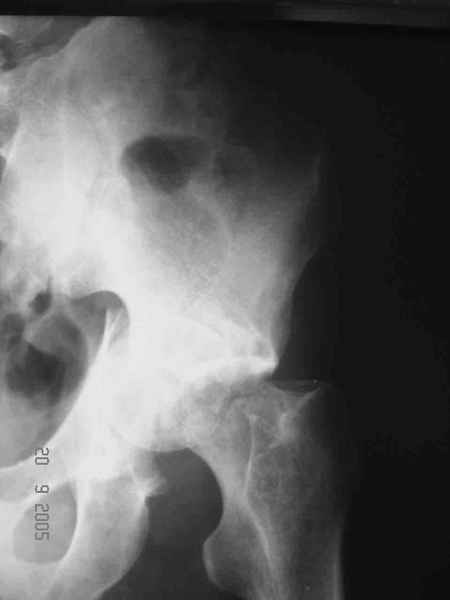

Два месяца нагрузки без костылей 19/12/03

Еще месяц 20/02/04

Больной 18 мая 2003 года в автоаварии получил перелом левой вертлужной впадины, вывих бедра. Госпитализирован в один из стационаров области.Вывих вправлен. В последствии бедро вывихивалось еще дважды. На консультацию был представлен снимок от 19.05.03г., больной переведен к нам 3.06.03г. Снимок при поступлении - перелом впадины, задне-верхний вывих бедра. 05.06.2003 г. выполнено открытое вправление вывиха левого бедра и остеосинтез стенки вертлужной впадины двумя винтами. Послеоперационный период без осложнений. Объем движений в левом тазобедренном суставе восстановился полностью. Выписан на амбулаторное лечение в удовлетворительном состоянии с рекомендациями 3 месяца ходить на костылях без нагрузки на оперированную конечность. На контрольных рентгенограммах левого тазобедренного сустава 13.10.2003 г. - признаки консолидации перелома; плотность, форма головки и состояние суставных поверхностей удовлетворительные. Разрешена дозированная осевая нагрузка, на конечность с использованием дополнительной опоры. 19.12.2003 г. больной обратился с жалобами на боли в левом тазобедренном суставе. На рентгенограммах левого тазобедренного сустава 19.12.2003 г., 20.02.04г. - асептичекий некроз головки бедра. 5.04.04г. - эндопротез. Сейчас ходит без трости, не хромает. Особенность эндопротезирования - при удалении винтов прослежена линия перелома заднего края впадины и предложено установить чашку несколько меньшего диаметра, чтобы она была покрыта несломанной частью.